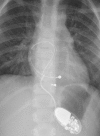

Atrioventricular block is classified as congenital if diagnosed in utero, at birth, or within the first month of life. The pathophysiological process is believed to be due to immune-mediated injury of the conduction system, which occurs as a result of transplacental passage of maternal anti-SSA/Ro-SSB/La antibodies. Childhood atrioventricular block is therefore diagnosed between the first month and the 18th year of life. Genetic variants in multiple genes have been described to date in the pathogenesis of inherited progressive cardiac conduction disorders. Indications and techniques of cardiac pacing have also evolved to allow safe permanent cardiac pacing in almost all patients, including those with structural heart abnormalities.

What is known: • Prevalence of congenital heart block of 1 per 15,000 to 20,000 live births. AV block is defined as congenital if diagnosed in utero, at birth, or within the first month of life, whereas childhood AV block is diagnosed between the first month and the 18th year of life. As a result of several different etiologies, congenital and childhood atrioventricular block may occur in an entirely structurally normal heart or in association with concomitant congenital heart disease. Cardiac pacing is indicated in symptomatic patients and has several prophylactic indications in asymptomatic patients to prevent sudden death. • Autoimmune, congenital AV block is associated with a high neonatal mortality rate and development of dilated cardiomyopathy in 5 to 30 % cases. What is New: • Several genes including SCN5A have been implicated in autosomal dominant forms of familial progressive cardiac conduction disorders. • Leadless pacemaker technology and gene therapy for biological pacing are promising research fields. In utero percutaneous pacing appears to be at high risk and needs further development before it can be adopted into routine clinical practice. Cardiac resynchronization therapy is of proven value in case of pacing-induced cardiomyopathy.